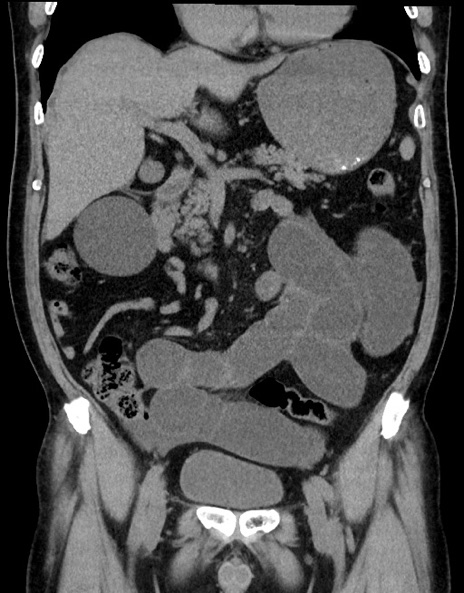

横断像

【症例】70歳代男性

【主訴】腹痛

【現病歴】今朝から腹痛あり。全体的に痛い。特に左上の方。排ガスが今日はない。冷や汗が出る。

【既往歴】直腸癌術後

【身体所見】左側腹部〜上腹部に圧痛あり。腹膜刺激症状明らかなではない。軽度反跳痛。左下腹部に術後瘢痕あり。

【データ】WBC 7700、CRP 0.02